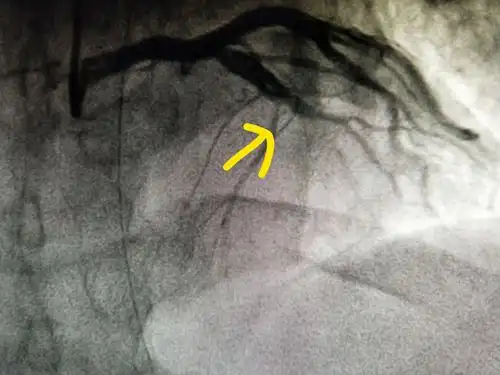

冠脉造影示:前降支中段100%闭塞,为此次心肌梗死之罪犯血管